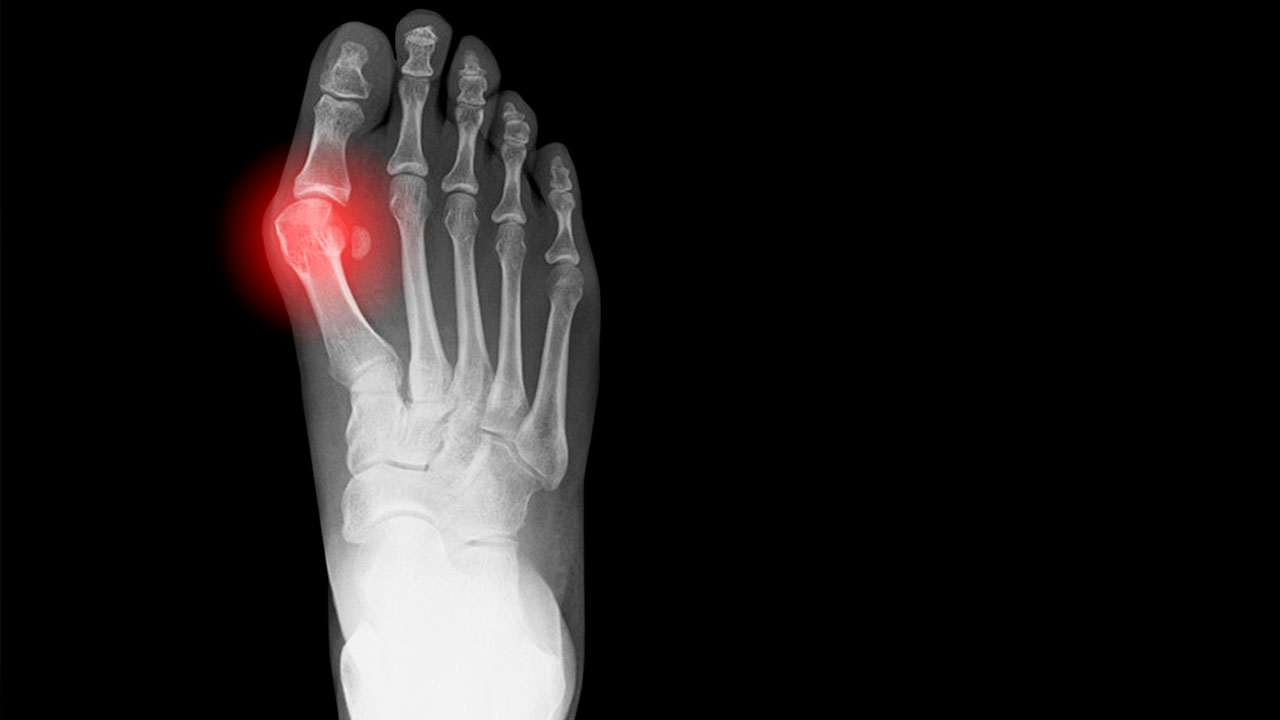

X-ray showing a bunion on a human foot.

• What is a bunion? A bunion (also called hallux valgus) is a bony bump at the base of the big toe that changes the shape of the foot. The misalignment of the big toe joint can cause the big toe to lean toward the second toe, creating the bump.